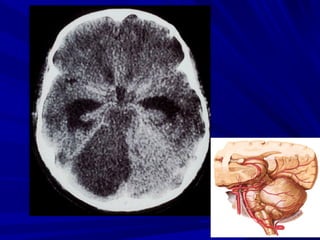

Phát hiện xuất huyếtPhát hiện xuất huyết

Xuất huyết là các vùng tăng đậm độ và có thể thấyXuất huyết là các vùng tăng đậm độ và có thể thấy

trong các bệnh lý:trong các bệnh lý:

Tụ máu ngoài màng cứng,Tụ máu ngoài màng cứng,

Tụ máu dưới màng cứngTụ máu dưới màng cứng

Xuất huyết màng nãoXuất huyết màng não

Xuất huyết não thấtXuất huyết não thất

Xuất huyết trong nãoXuất huyết trong não

Phân biệt hoá vôi và xuất huyết nhỏ vùng nhân nềnPhân biệt hoá vôi và xuất huyết nhỏ vùng nhân nền

Phân biệt xuất huyết cầu não với hình ảnh nhiễuPhân biệt xuất huyết cầu não với hình ảnh nhiễu